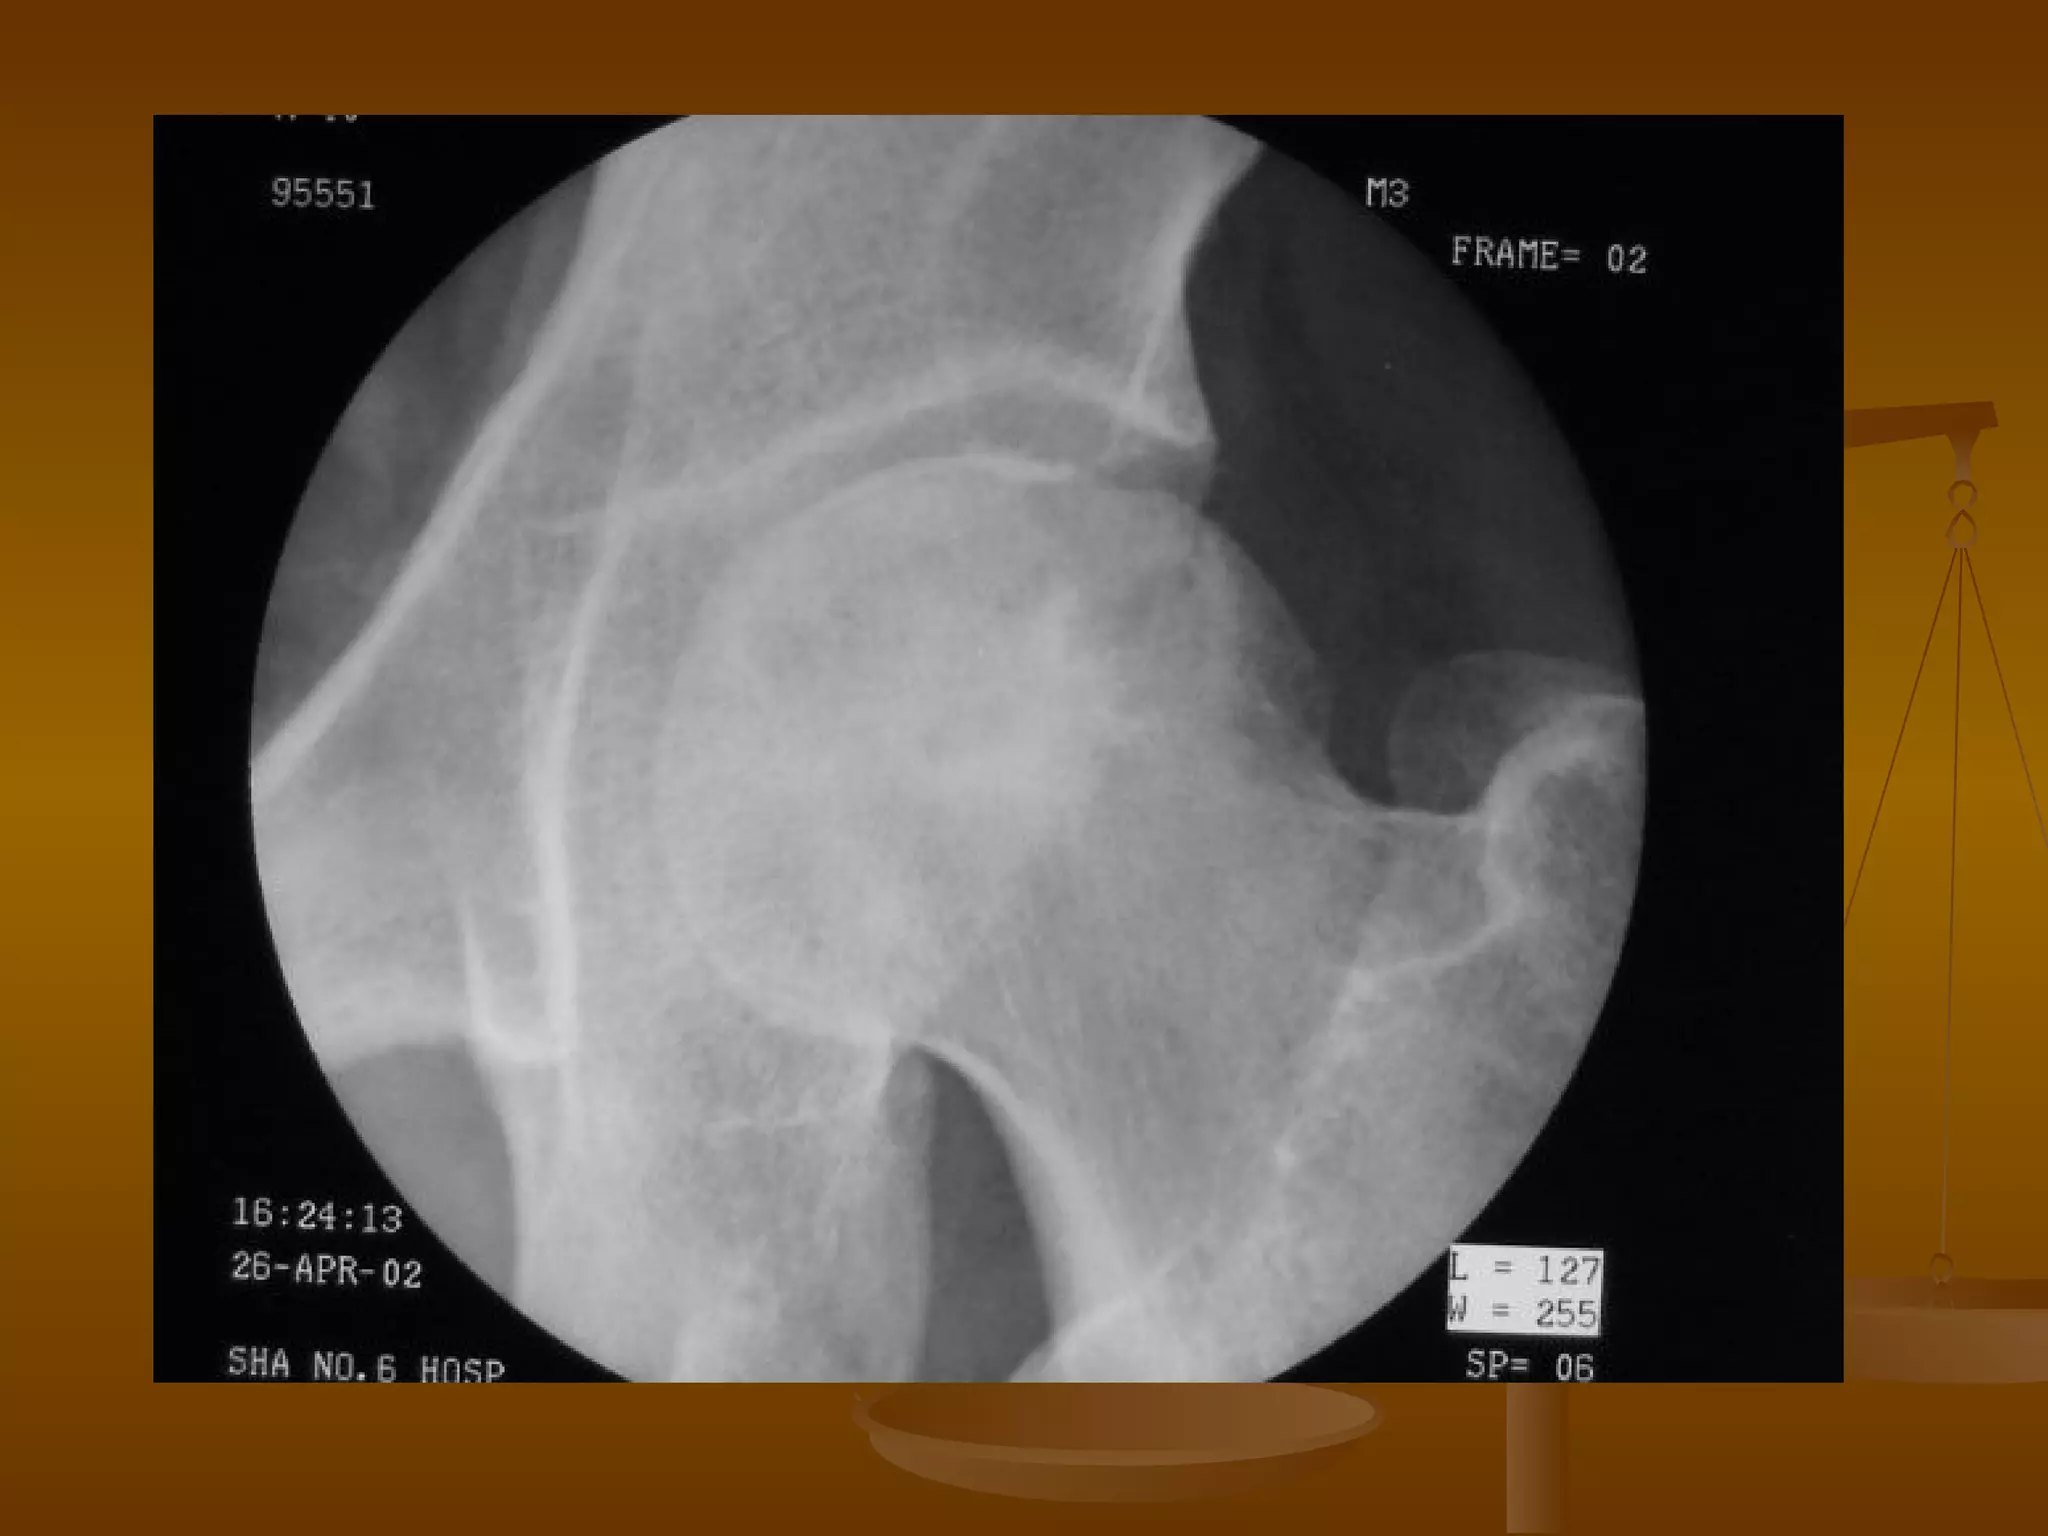

DSA 诊断 早期:选择性旋股内侧动脉造影,可见上、下关节囊动脉迂曲、变细、阻塞或不充盈,静脉淤滞。 中、晚期:股骨头出现囊变或变形时,上关节囊动脉阻塞或再通,动脉变细,骨坏死周围出现血管增多区。